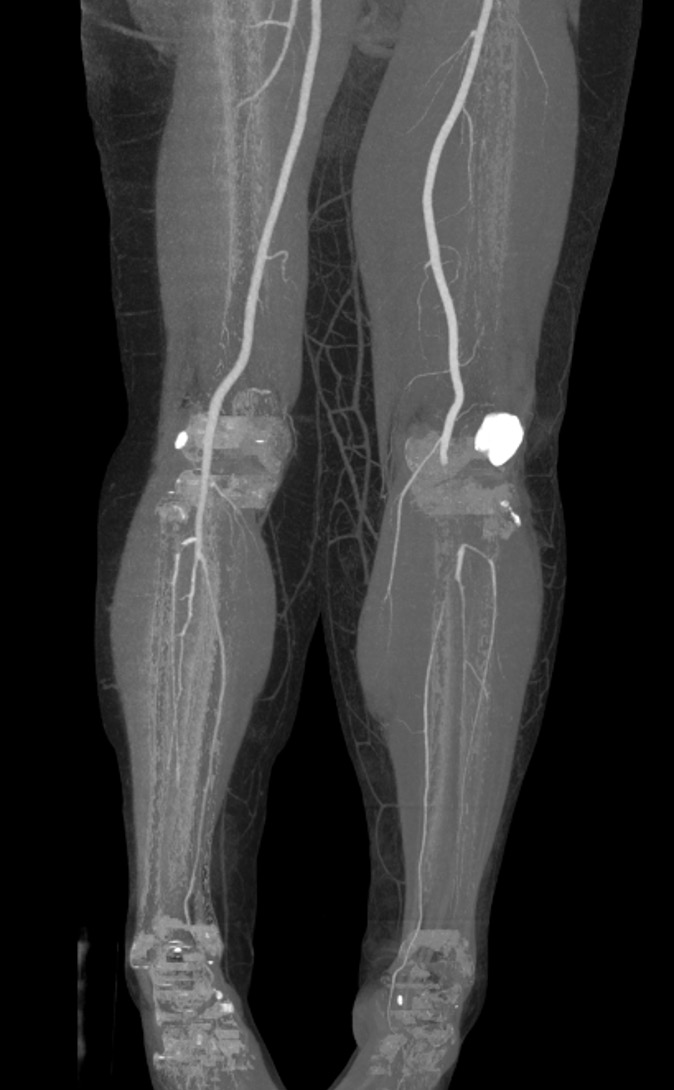

Normal CT angiogram Popliteal artery stenosis following knee dislocation

Popliteal artery transection following left knee dislocation

Advantages

- readily available, non invasive

- extremely accurate

- also used confirm the site and mechanism of injury

- multi-detector CT

- 100% sensitive and specific in detecting clinically significant arterial injury

Gakhal et al. Vascular and Interventional Radiology 2009

- CTA signs of lower extremity vascular trauma